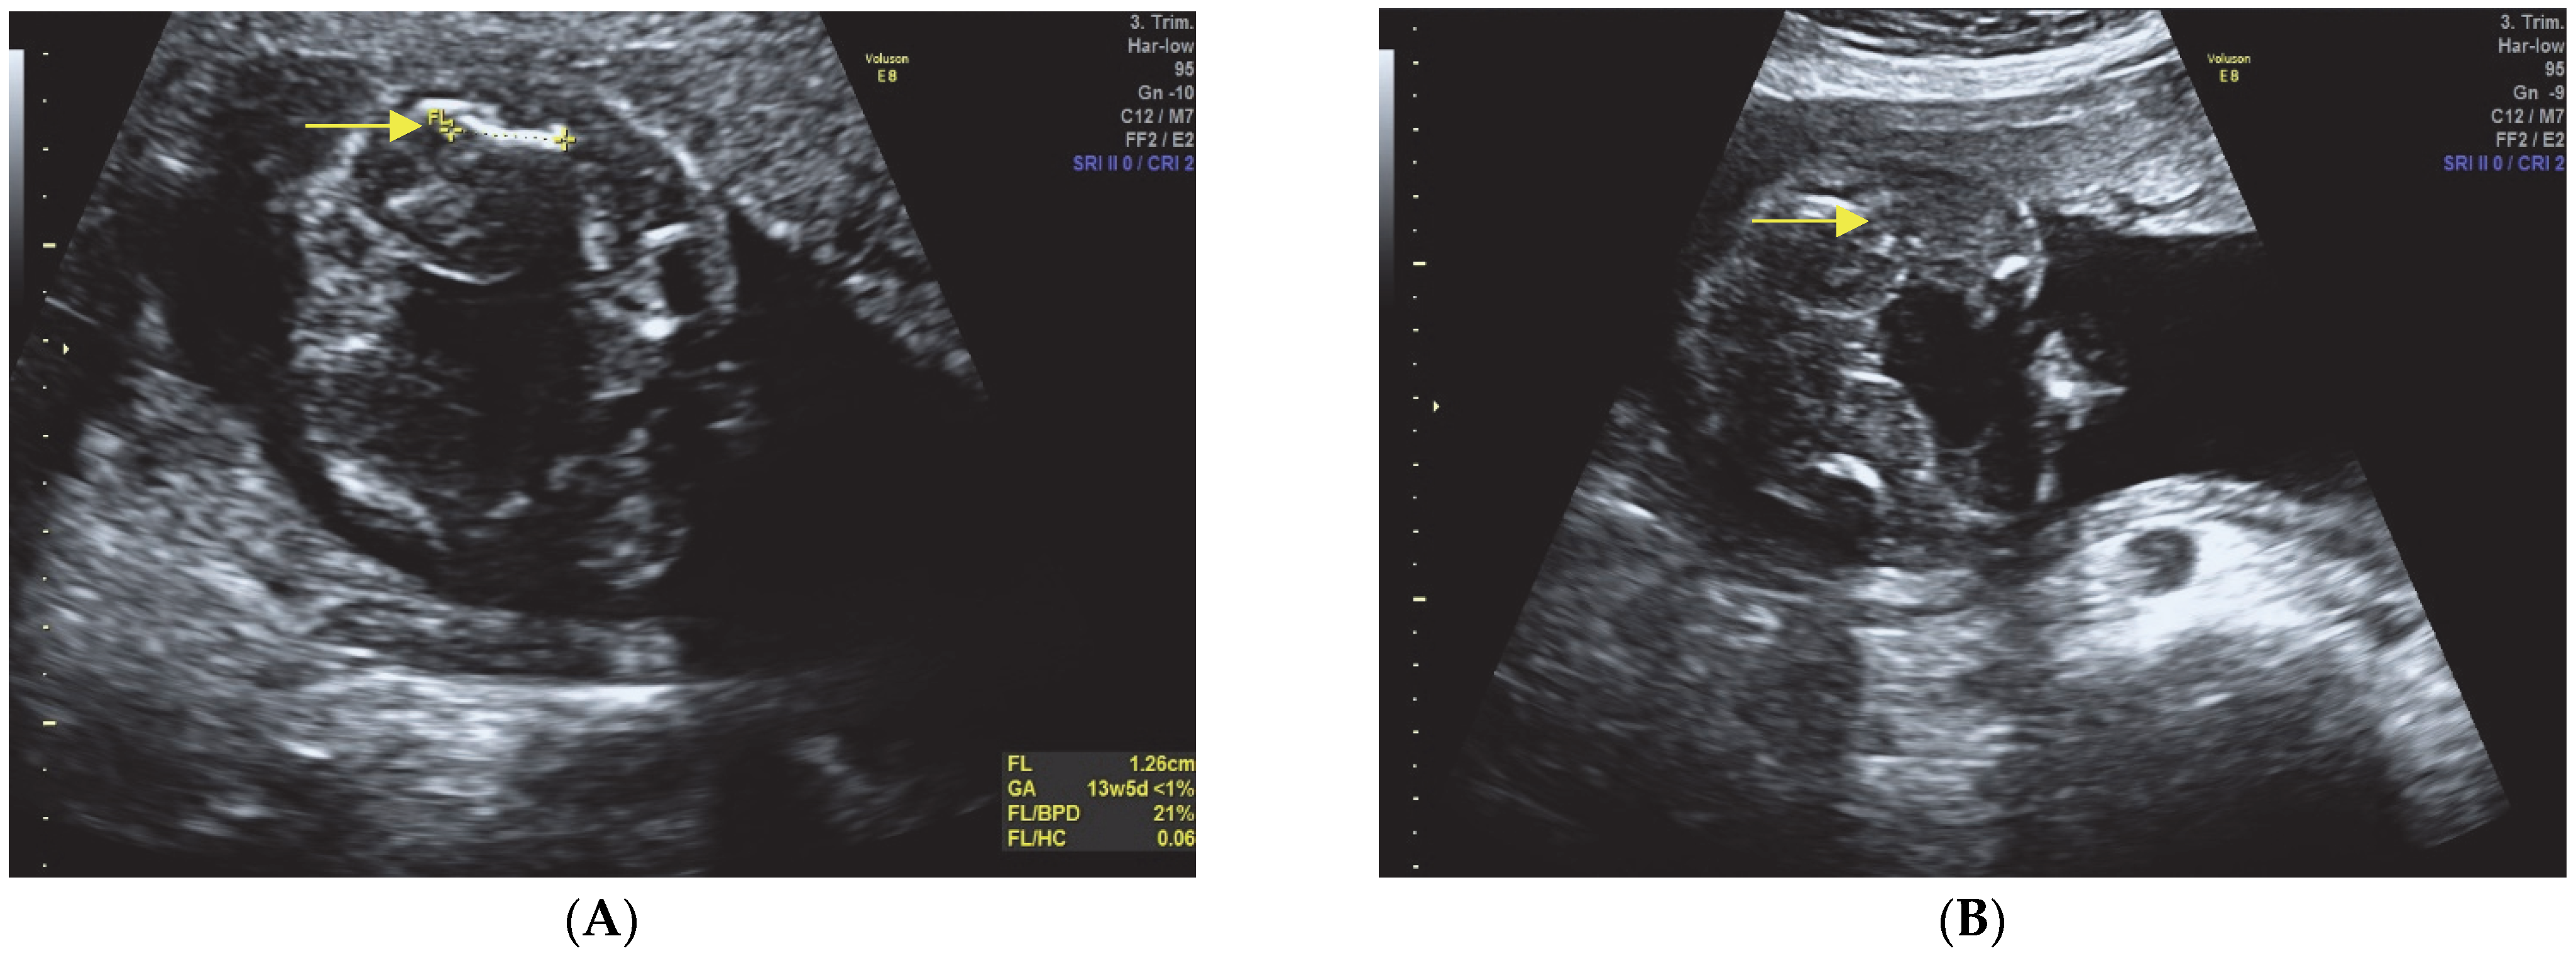

:- Short limbs with severe micromelia affecting all four limbs.

- Remarkably bowed femur and humerus.